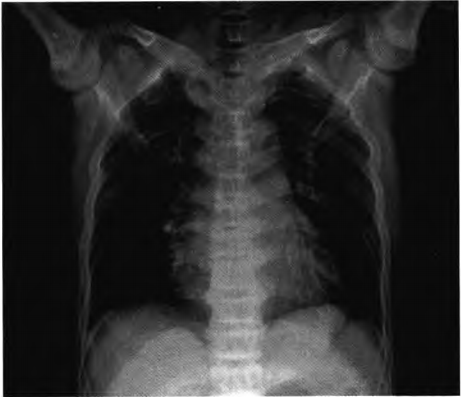

图1.术前胸椎正位X线片示椎体上下缘增厚致密,中央部密度相对较低,呈现“夹心蛋糕征”

X线检查:①全身多发骨密度增高,骨小梁粗糙、模糊,骨皮质厚,髓腔窄小;②椎体呈“夹心蛋糕样”特征性改变;③两侧髂骨翼呈典型“同心环状征”;④双侧髋关节、膝关节软骨下骨密度增高,关节间隙窄(见图1~2)。